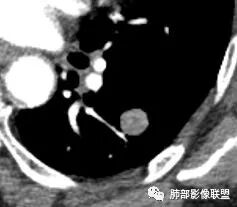

胸CT:左下肺实性结节,密度均匀,边缘光滑,未

毛刺、分叶、晕征及棘突样改变,增强可见血管贴边,静脉期较动脉期强化。

定位 左肺下叶背段斜裂旁实性小结节,边界清晰,密度尙均匀,未见脂肪钙化,与支气管关系不密切,可见肺血管贴边,增强呈轻中度强化,平扫47hu 动脉期48 静脉期67hu,

CT值46H

增强67HU

动脉期弱一些,后期强化明显一些

动脉期边缘斑点状、结节状强化为主

后期趋向于均匀强化

动脉期测量区域——中央,不是强化区域

其实强化还算是中度,幅度超过20HU